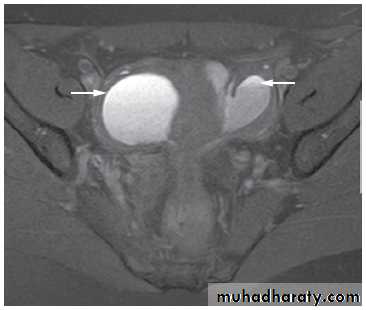

On MRI There are characteristic appearances due to recurrent haemorrhage into endometriomas and there is often in-drawing of the rectum towards the pouch of Douglas due to the development of fibrous adhesions.